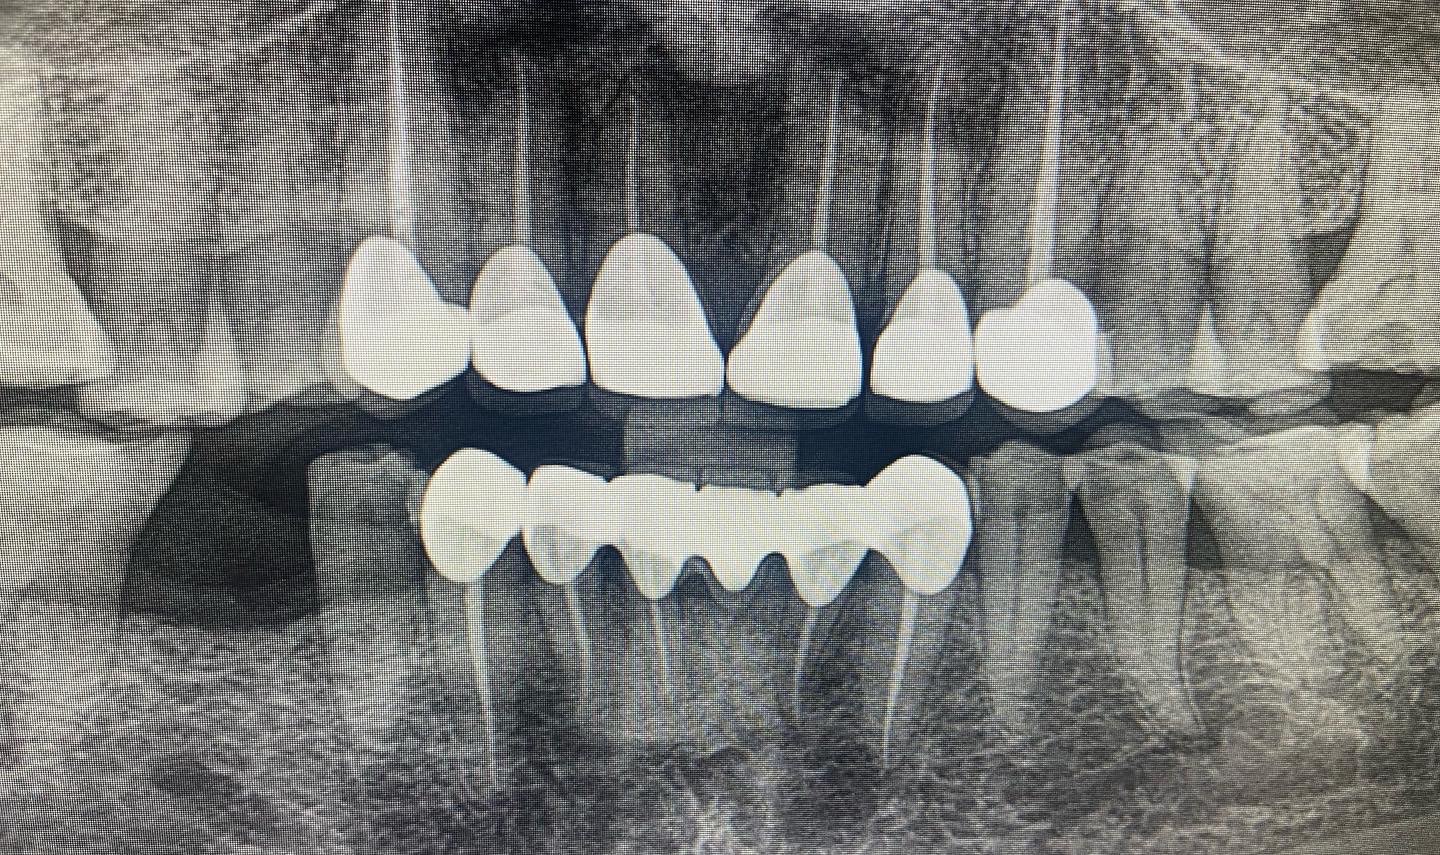

At Dentasia, we offer a range of dental X-ray in Kolkata, West Bengal services to meet all your diagnostic needs. Each type of dental X-ray provides different insights into your oral health: Teeth X-Ray/RVG: Also known as Radiovisiography (RVG), this teeth X-ray focuses on individual teeth and their immediate surroundings. It is ideal for detecting issues such as decay, root problems, and infections. Bitewing X-Rays: These dental X-rays show the upper and lower teeth in a specific area of the mouth. They are particularly effective for identifying cavities between teeth and assessing the level of bone support around your teeth. Panoramic Dental Imaging/OPG: This dental X-ray in West Bengal captures a broad view of your entire mouth, including all teeth, jaws, and surrounding structures. It is useful for evaluating overall dental health, planning orthodontic treatment, and detecting issues like impacted teeth or jaw disorders. You can also read about How long do dental implants last ? here CBCT (Cone Beam Computed Tomography): CBCT provides three-dimensional imaging of your teeth, jaws, and surrounding anatomy. This advanced dental X-ray technique is essential for detailed assessments required for complex cases such as implant planning, bone structure evaluation, and precise orthodontic treatment.